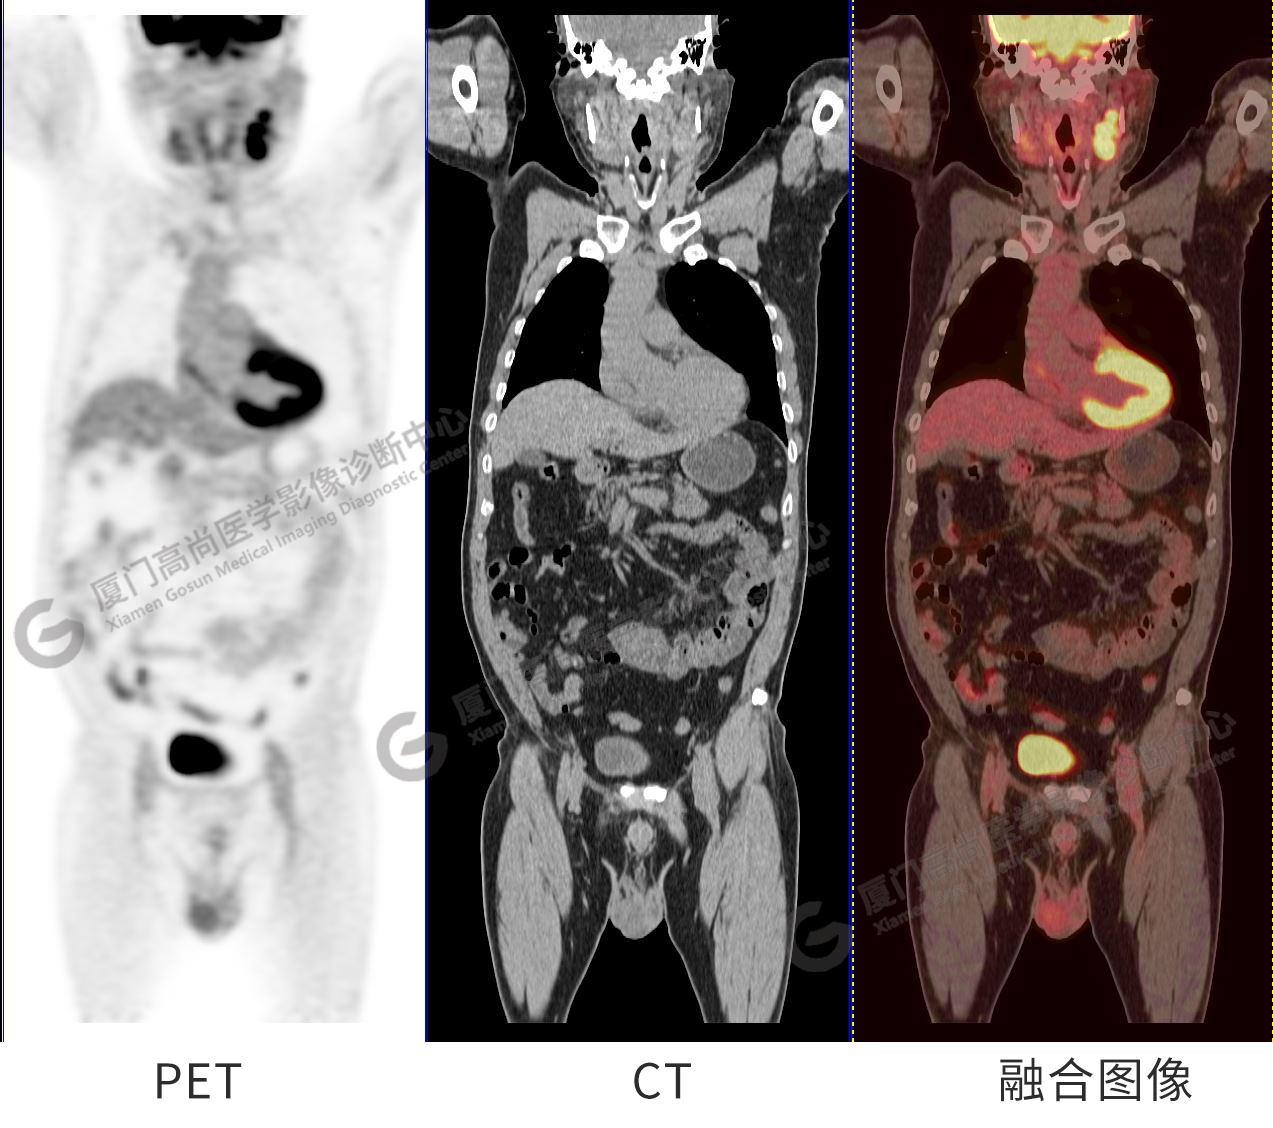

PET/CT影像圖

圖1:PET/CT全身圖像

圖2-9:雙側(cè)鎖骨區(qū)、縱隔、右側(cè)內(nèi)乳區(qū)、腸系膜緣、腹膜后、雙側(cè)髂血管旁及盆腔多發(fā)腫大淋巴結(jié)影,代謝不同程度增高,考慮為轉(zhuǎn)移。

圖10-11:子宮頸軟組織腫塊,代謝異常增高,考慮為宮頸癌。

圖12-13:延遲2小時后,宮頸腫塊糖代謝進一步增高。